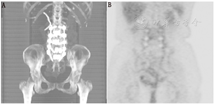

白细胞在感染病灶和骨髓中均有浓聚,因此标记白细胞显像很难对两者进行区分。99Tcm-硫胶体骨髓显像可用于两者的鉴别。这2种放射性药物都会在骨髓中浓聚,但只有标记的白细胞会在感染病灶中浓聚。当标记白细胞图像上的放射性浓聚区在骨髓显像中表现为放射性缺损时,可诊断为骨髓炎(图2,图3)。标记白细胞/骨髓显像的准确性约为90%[5]。标记白细胞在注射后3~4 h和20~24 h的双时相显像已被推荐作为标记白细胞/骨髓显像的替代方法[6]。

2.糖尿病足骨髓炎。糖尿病患者在出现明显的足部感染时全身可无反应,且骨髓炎的诊断易被临床忽视[34]。标记白细胞显像是放射性核素诊断糖尿病足骨髓炎的"金标准"。111In标记白细胞平面显像的灵敏度和特异性分别为72%~100%和67%~100%。99Tcm标记白细胞平面显像的灵敏度和特异性分别为86%~93%和80%~98%[3]。放射性标记的抗粒细胞抗体和抗体片段的诊断价值相似[35,36,37]。

SPECT/CT在疑似足骨髓炎患者中具有一定的临床价值[38,39,40,41,42]。Heiba等[39]发现联合111In标记白细胞/99Tcm-甲基双膦酸盐SPECT/CT显像和骨髓显像诊断的准确性明显高于平面显像和单核素SPECT/CT显像,且有助于标记白细胞精确定位病灶和提高阅片者的信心。另一项研究表明,双核素SPECT/CT显像在感染的诊断和定位方面比传统显像方法更准确,有助于指导患者的治疗,并与较短的住院时间相关[40]。

Filippi等[41]报道称99Tcm标记的白细胞SPECT/CT显像改变了一半以上患者的诊断,确诊或排除了骨髓炎,并准确划定了感染范围(图5)。Erdman等[42]制订了99Tcm标记白细胞SPECT/CT显像的严重程度指数,其与治疗效果成反比,且根据严重程度指数将骨髓炎患者分为阳性或阴性组进行研究后,预后评估更为准确。